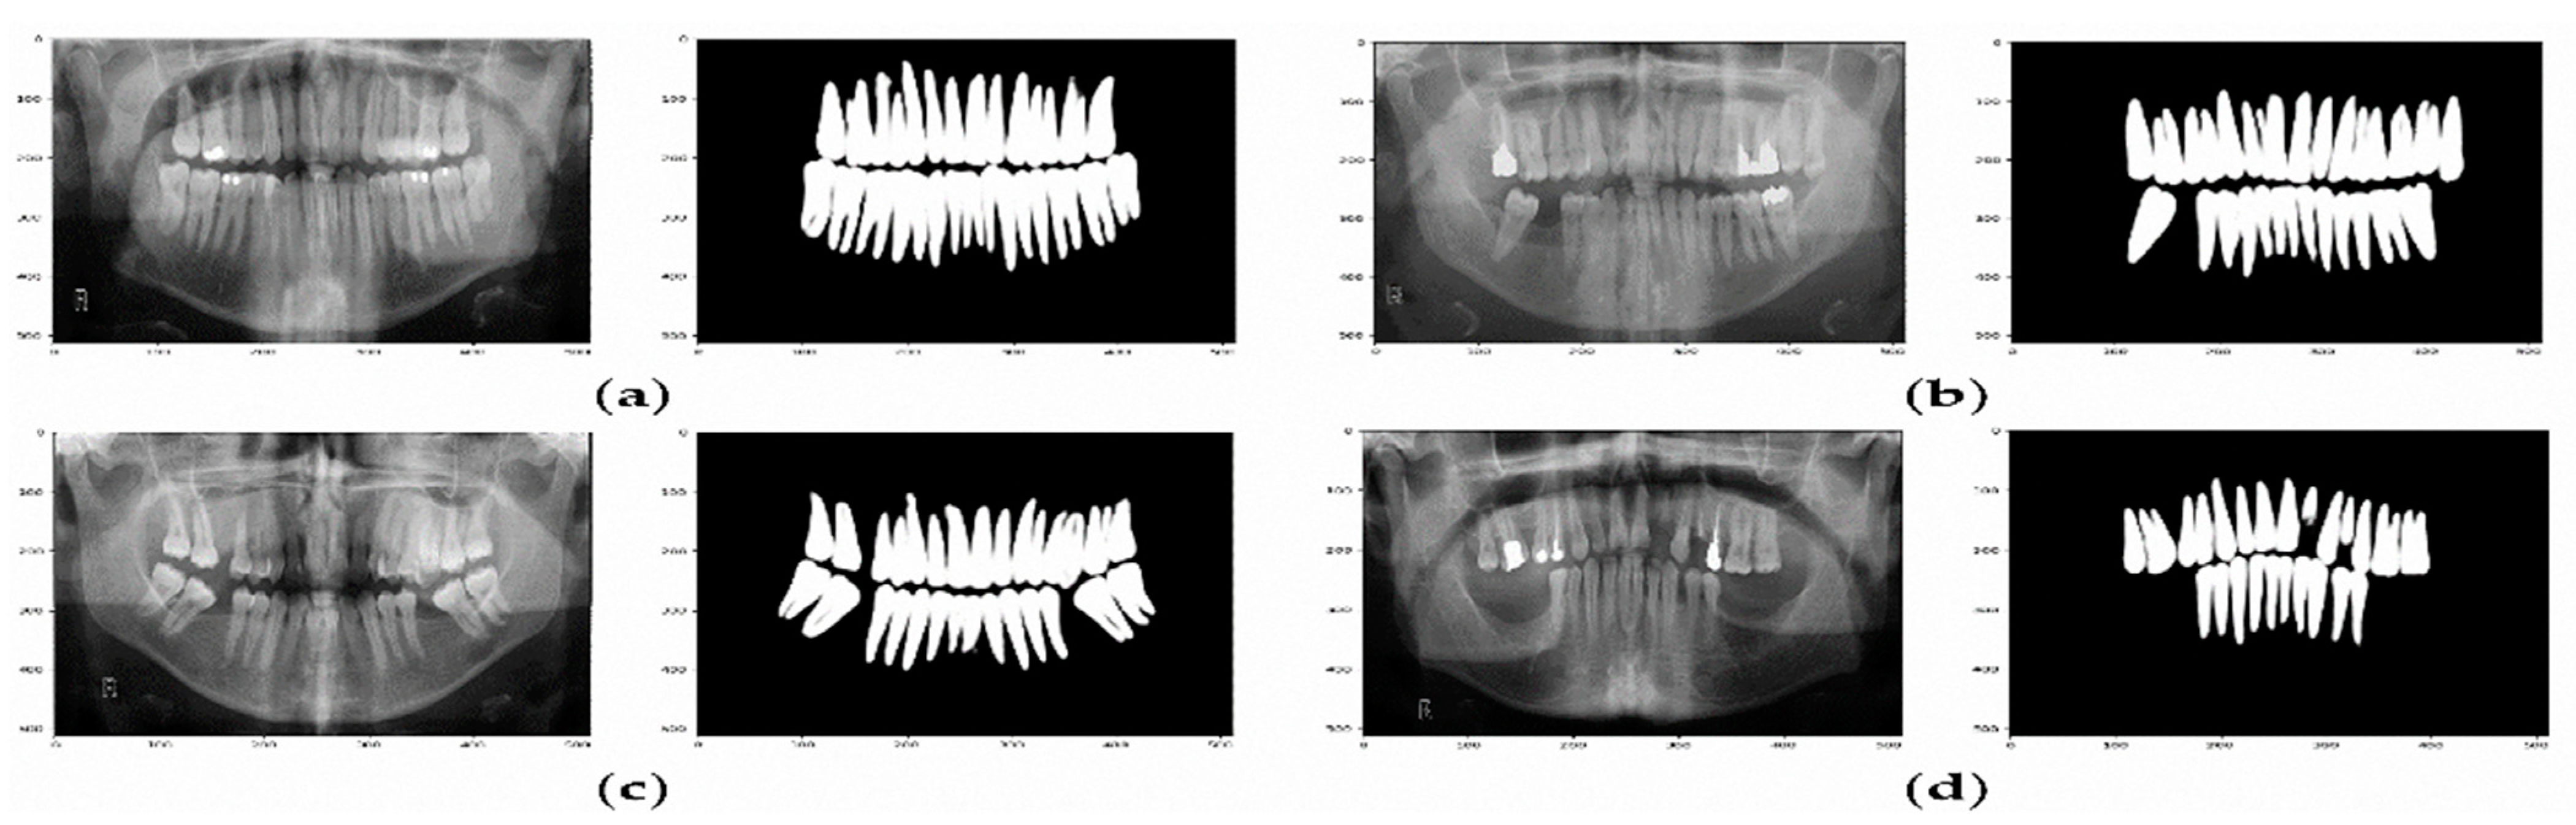

The confusion matrix presented in Table 4 and Figure 8 show that the U-Net model can predict the missing teeth (class 1) perfectly.

Figure 8.

Example of predicted masks using U-Net model. (a) The X-ray image and the predicted binary mask for normal teeth. (b–d) Various X-ray images and their predicted binary masks for missing teeth.